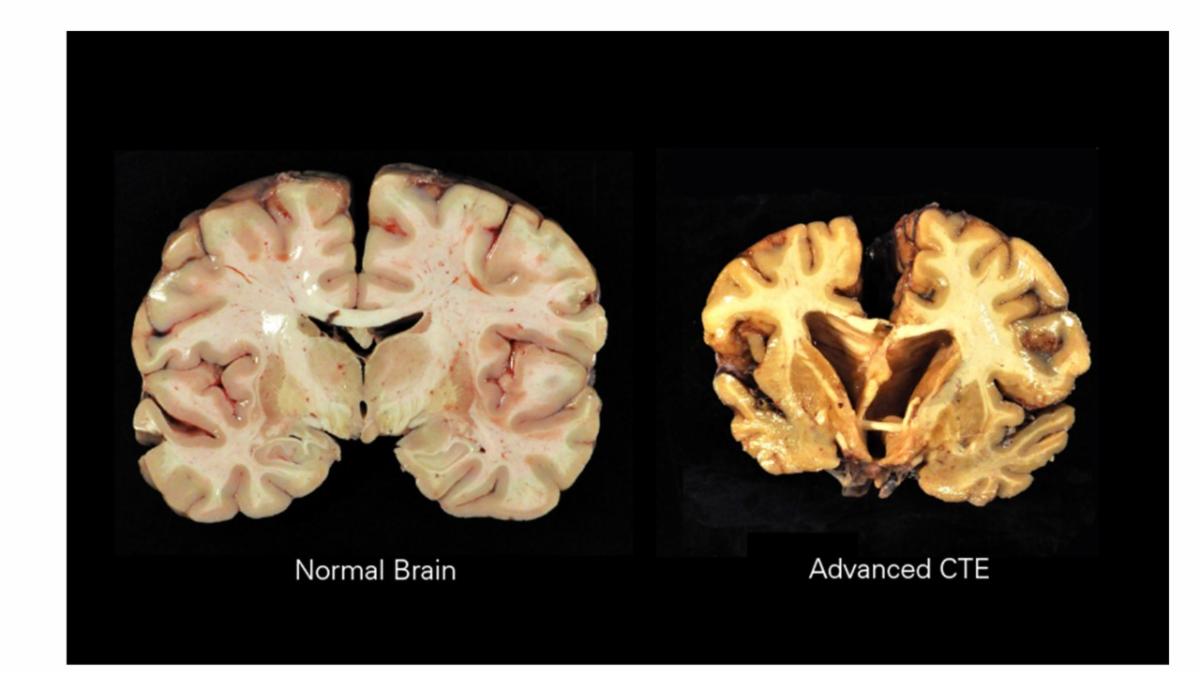

Chronic Traumatic Encephalopathy (CTE) can only be definitively diagnosed after death through brain examination. While it is impossible to know exactly how many people are living with CTE, studies suggest a significant number of individuals with a history of repetitive head impacts, particularly in contact sports and the military, may be living with CTE or experiencing symptoms related to it.

- CTE is a progressive neurodegenerative disease linked to repetitive head trauma, often seen in athletes, military veterans, and others exposed to repeated brain injuries.

- It’s characterized by the accumulation of “tangles” and abnormal tau protein in specific brain regions, which disrupts normal brain function.

- Currently, CTE can only be definitively diagnosed after death through brain tissue analysis.